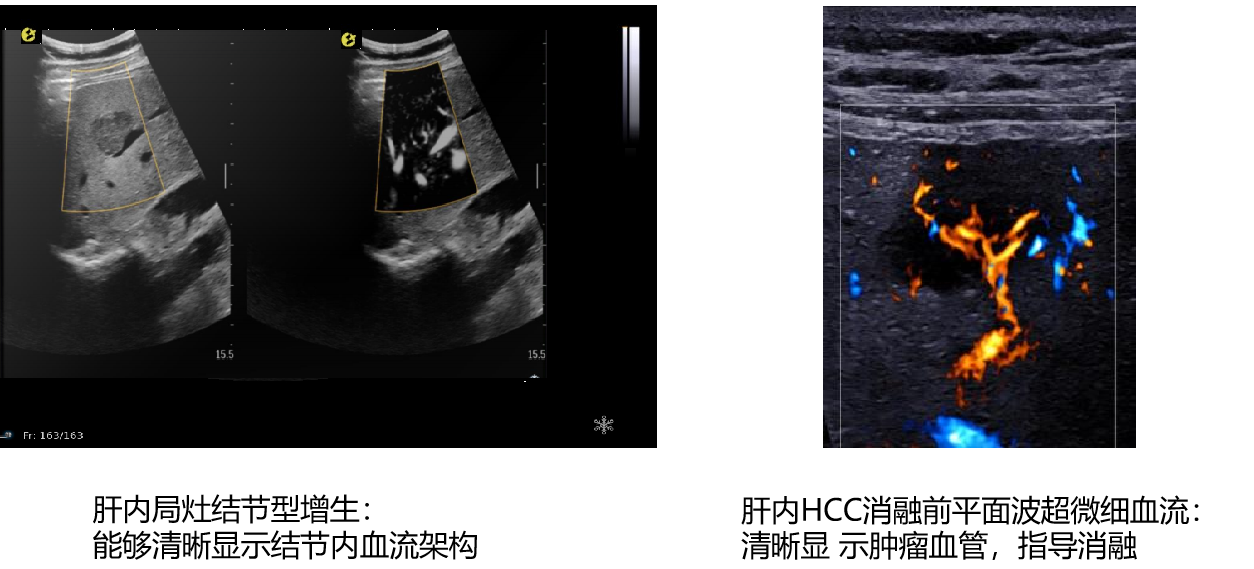

平面波超微细血流显像

能够提供更多真实的组织细小及末梢血管的血流信息,直观的观察组织内部的血管架构及血流形态的情况,提供临床更多有价值的诊断信息。

临床应用:

肿瘤鉴别诊断(肝脏、肾脏、甲状腺、乳腺、  涎腺等)

淋巴结评价(炎症、肿瘤)

肌骨系统临床诊断和疗效监测(关节、滑膜、韧带、肌肉炎症、 损伤等)

斑块内新生血管评估

超声介入术前进针方案提供血流参考信息

超声介入术后疗效评估

image.png